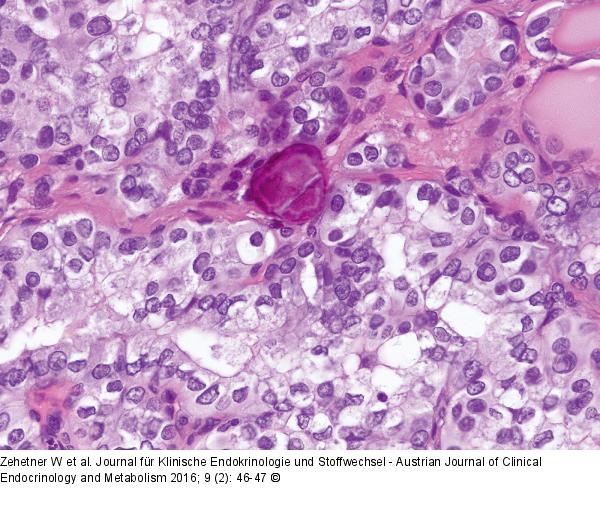

Abbildung 3: Schilddrüsenkarzinom HE x 400: papill. SD-Ca, prismatische Zellen mit anisokariotischen teilweise milchglasartigen Kernen, Pseudoinklusionen und einzelnen Kernkerben |

Abbildung 3: Schilddrüsenkarzinom

HE x 400: papill. SD-Ca, prismatische Zellen mit anisokariotischen teilweise milchglasartigen Kernen, Pseudoinklusionen und einzelnen Kernkerben |